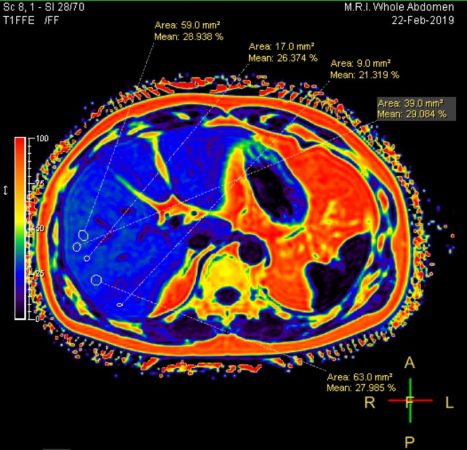

- การตรวจค่าการทำงานของตับ จากเอนไซม์ AST (SGOT) และ ALT (SGPT) ที่ร่างกายสร้างขึ้นเมื่อตับเกิดความเสียหาย เอนไซม์ Alkaline phosphatase (ALP), Gamma GT (GGT) และบิลิรูบิน (bilirubin) เพื่อดูความผิดปกติของตับและการอุดตันของท่อน้ำดี ร่วมกับการตรวจทางรังสีที่ตับและช่องท้อง ได้แก่ อัลตราซาวด์ช่องท้อง (Abdominal Ultrasound) โดยใช้คลื่นความถี่ และการตรวจด้วยเครื่องแม่เหล็กไฟฟ้า หรือการ MRI ช่องท้องความละเอียดสูงแบบไม่ฉีดสี (MRI Whole Abdomen Non-contrast) ช่วยในการประเมินความผิดปกติต่างๆ เช่น เปอร์เซ็นต์ไขมันพอกตับ, ภาวะไขมันพอกตับ (Fatty Liver) และภาวะไขมันพอกตับอ่อน (Fatty Pancreas), ก้อนเนื้อที่ผิดปกติ หรือเนื้องอกที่อาจพัฒนากลายเป็นมะเร็ง, ความผิดปกติที่ท่อน้ำดีและนิ่วในถุงน้ำดี, ฝีในตับ และการไหลเวียนของเส้นเลือดภายในช่องท้อง

การตรวจสุขภาพตับอย่างสม่ำเสมอ ช่วยให้สามารถวางแผนป้องกันไม่ให้ตับแข็ง และตับอ่อนแข็ง ซึ่งถือเป็นความเสียหายอย่างถาวรของเนื้อเยื่อตับ รวมถึงช่วยให้ค้นพบมะเร็งได้ตั้งแต่ระยะเริ่มต้น เพื่อให้เกิดการรักษาได้อย่างทันท่วงทีไม่ให้เกิดการแพร่กระจายของมะเร็ง